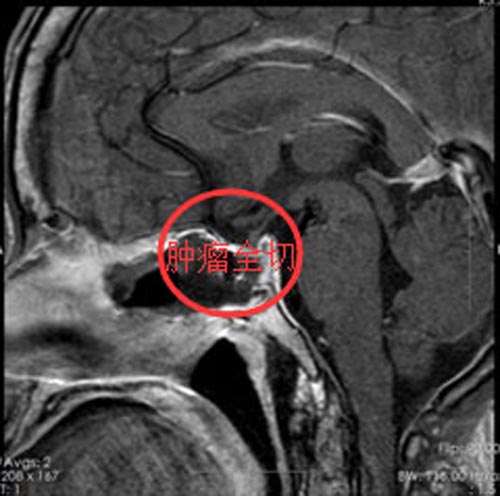

既兴奋又疑惑的李女士接受了“内镜经鼻蝶鞍区占位切除术”,手术非常顺利,手术效果大大超出了她的预期,不但看不出有伤疤,头痛症状也消失了。

▲手术后